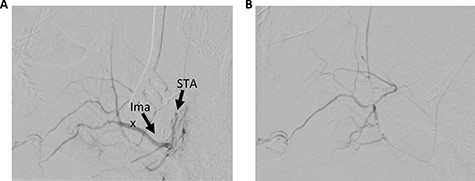

The patient underwent a left preauricular incision to isolate the STA from surrounding parotid parenchyma by the Head & Neck Surgery team. Under microscopic guidance, the STA was cannulated with an 18-gauge angiocatheter (Fig. 2) by the Neurosurgery team, which was secured in place with 2-0 silk suture. A rotating hemostatic valve (Abbott Laboratories, Chicago, IL) was attached to the angiocatheter and a retrograde angiogram was performed, confirming STA access (Fig. 3A). An Echelon 10 microcatheter (Medtronic, Minneapolis, MN) and a Synchro 14 microwire (Stryker, Kalamazoo, MI) were then used to select the proximal left IMA for digital biplane angiography. Hand-injected control angiography confirmed appropriate microcatheter positioning, demonstrating opacification of the left IMA and branches, with nonspecific contrast blush including the left sphenopalatine arteries. Thereafter, liquid embolization using Onyx® Liquid Embolic System (Medtronic, Minneapolis, MN) was performed to occlude the IMA. A final angiogram demonstrated satisfactory occlusion of the left IMA without evidence of extravasation, aneurysm or pseudoaneurysm (Fig. 3B). The STA was decannulated and ligated, and the preauricular incision was closed primarily.

Left STA injection. (A) Pre-embolization and (B) post-embolization. Ima, internal maxillary artery.